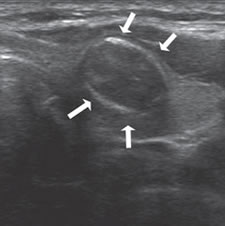

7. Invasión local y adenopatías

La extensión de la masa fuera de la cápsula, la infiltración de la tráquea o de los músculos pretiroideos es muy sugerente de malignidad (Figura 15a). Asímismo, la presencia de adenopatías con características típicas, debe hacer sospechar que el nódulo tiroideo es maligno. Los cánceres papilares de la tiroides son propensos a dar metástasis precozmente a los linfonodos cervicales y hasta la mitad de todos los pacientes pueden presentar adenopatías concomitantes. En 15% de los pacientes, el único signo de un cáncer tiroideo papilar oculto puede ser la detección de adenopatías. La mayoría de las metástasis ocurren ipsilateralmente al tumor primario en los grupos III y IV de la cadena yugular interna y del grupo VI del compartimiento central. En la ecografía, los linfonodos metastáticos pueden tener una forma redondeada o globular, una arquitectura con elementos sólidos o quísticos, con o sin microcalcificaciones y pérdida del hilio (Figura 15b y c). El “Doppler color” puede demostrar vasos capsulares de distribución caótica en reemplazo de los vasos hiliares normales (Figura 15d). Las adenopatías hiperecogénicas son sospechosas de cáncer papilar (Figura 16a). Los linfonodos normales en algunos grupos como el VI y el VII no se ven ecograficamente, de manera que si se hacen visibles, en el mismo lado del tumor, independiente del tamaño que tengan hay que considerarlos como adenopatías metastásicas (Figura 16b)

Figura 15. a) Cáncer papilar sólido de bordes lobulados (flechas) que muestra una gruesa calcificación central (flecha abierta) y múltiples

microcalcificaciones; b) Adenopatía cervical del grupo IV del mismo paciente (figura 15 a), hiperecogénica, con elementos quísticos (flecha

blanca) y microcalcificaciones agrupadas (flechas negras), típica de cáncer papilar; c) Adenopatías de grupo IV de un cáncer papilar, de

forma redondeada, hiperecogénicas, con pérdida del hilio, una anterior a la arteria carótida común (flecha) y otra lateral a la vena yugular

interna (flecha abierta); d) Corte sagital de la adenopatía lateral de la imagen 15 c), que en “doppler color” muestra vascularización patológica

y pérdida del hilio.